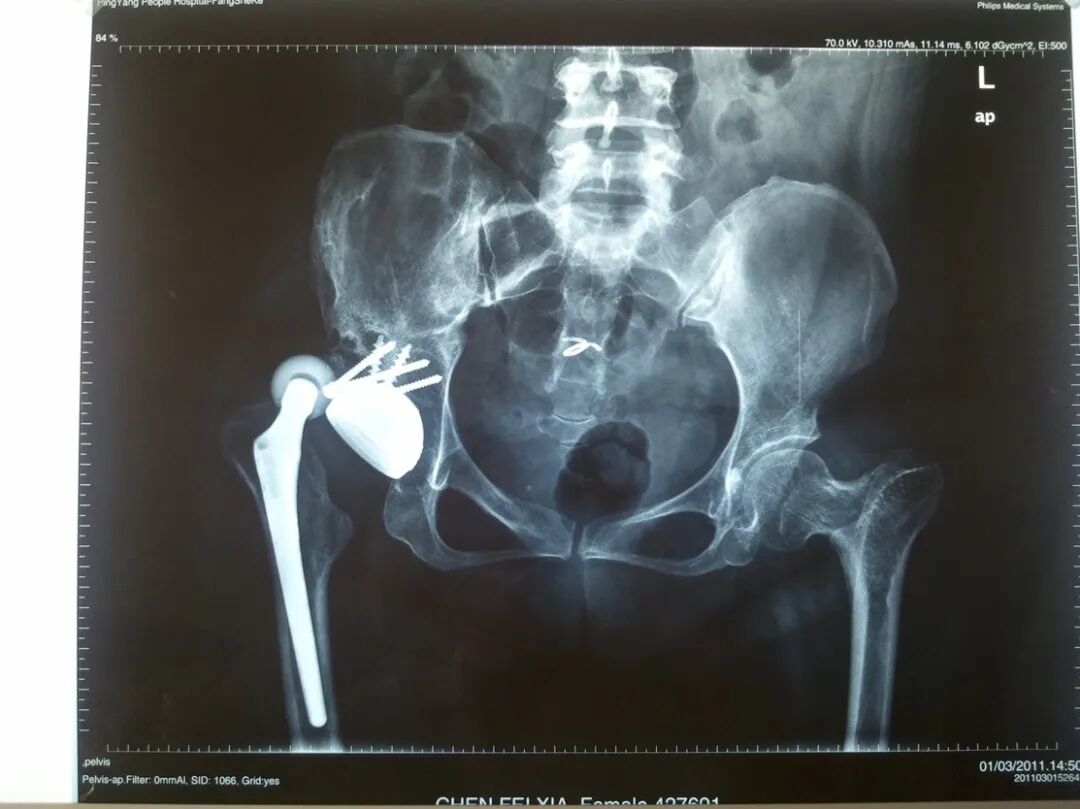

女性患者,48岁,右髋疼痛25年,加重1年

术后5天,脱位

术后4月,再一次脱位